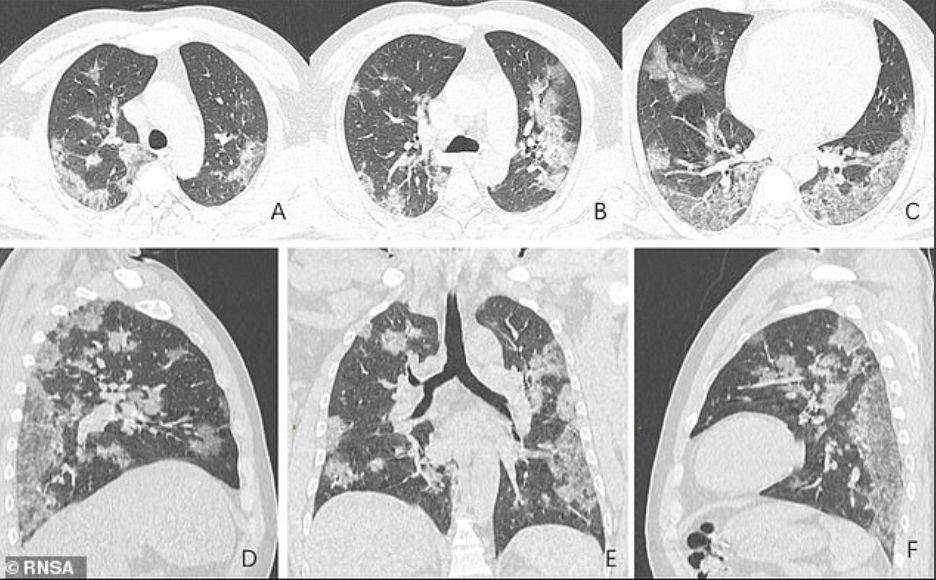

二人肺部的X光片近日曝光,可见肺部出现磨砂玻璃状影像(ground-glass opacities),整个肺部都受到了严重的影响。

从他们肺部的X光片可见,肺部已出现磨砂玻璃状影像。出现这种情况是因为肺部被脓液、血水等物质填满,并从而导致患者呼吸困难。这情况通常与软组织增厚或肿胀有关。当比较图像A和图像F时,很明显,随着时间的流逝,人肺部中的液体变得越来越多,也越来越明显。